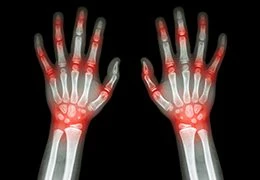

Each person on our team has years of clinical experience in the field of regenerative medicine, allowing us to treat patients of all ages and with a variety of conditions – including knee pain, shoulder pain, elbow pain, back pain, and other joint pain conditions. From the moment you call us for your initial consultation to when you're working toward a healthier future, we will always be here to help you every step of the way.

If all this sounds like it might describe you too, then call us today to set up a consultation so we can help you feel better tomorrow. We'd be happy to show you how non-surgical regenerative treatment is changing how we deal with conditions both small, such as joint pain or back pain, or large like knee pain,  arthritis pain or hip replacement recovery.